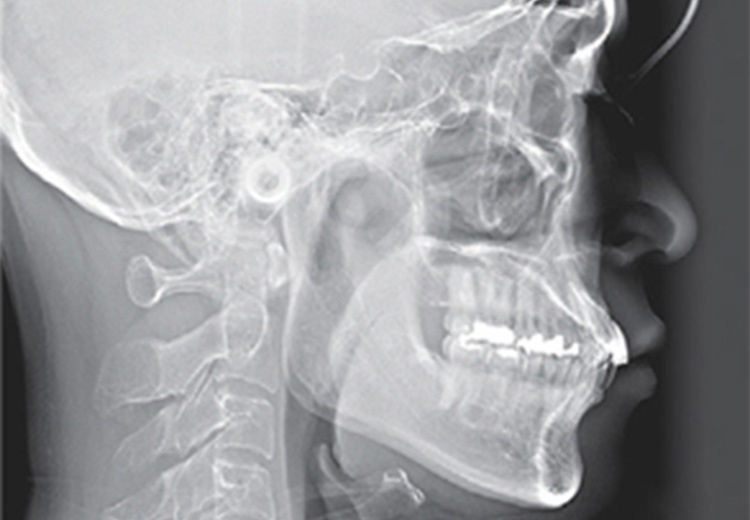

セファロ

矯正治療専用のレントゲンで、歯や顎だけでなく頭部全体を撮影します。

「上下の顎の大きさや位置のズレ」「顎の形状」「歯の傾き」「口元のバランス」などを詳細に把握できるため、骨格の特徴やかみ合わせを正確に分析することが可能となります。